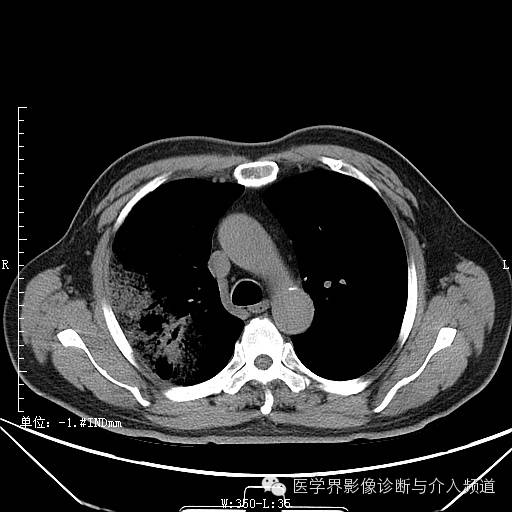

初诊

初诊:右肺上叶见大片实变影,呈磨玻璃状及网状,可见“充气支气管征”,纵隔窗可见实变影范围有所缩小,呈蜂窝状,局部支气管走行不自然,管壁不光滑。